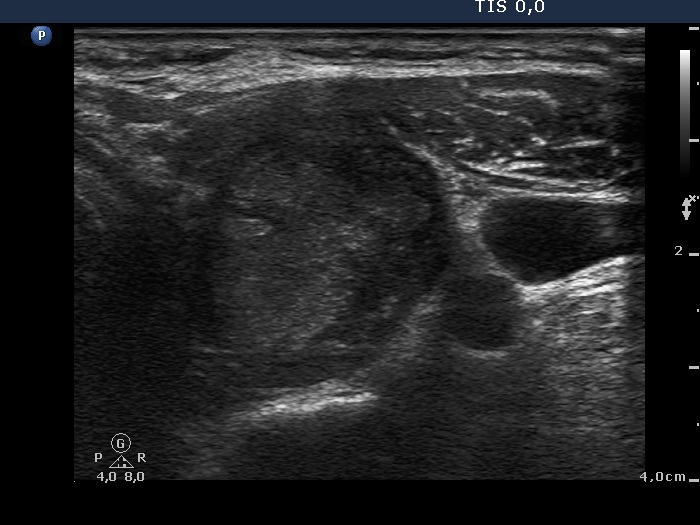

First examination (first and second rows of images):

Clinical presentation: A 41-year-old woman was referred for an evaluation of complaints suggesting hyperthyroidism.

Palpation: Both lobes were enlarged and moderately firm.

Results of blood tests: hyperthyroidism (TSH undetectable, FT4 51.8 pM/L).

Ultrasonography. A diffusely hypoechogenic thyroid was found with multiple lesions. There was a hypoechogenic lesion in the dorsal part of the right lobe. This lesion showed taller-than-wide and longer-than-wide shape. The left lobe had two lesions which were more echogenic than the non-nodular part of the lobe, however less echogenic than a normal, healthy thyroid.

Cytology was performed from the hypoechogenic nodule found in the right thyroid and from one of the hyperechogenic nodules in the left lobe. Cytological diagnosis: benign pattern corresponding to hyperthyroidism.

TSAb was elevated 11.0 U/mL (normal value below 1.5) while scintigraphy excluded the possibility of autonomy.

Thyrostatic therapy was started. We told the patient that the final solution could be surgery.